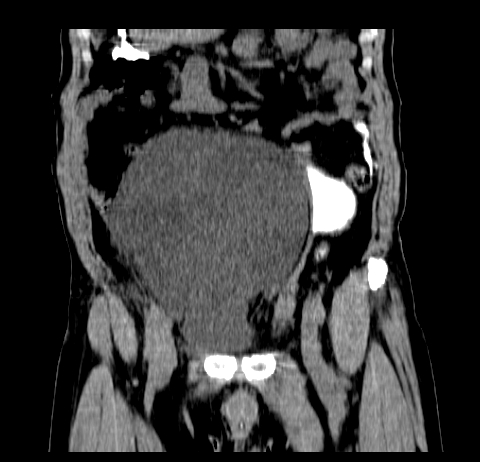

标题: CT19729B:男,74岁,因腿疼就诊,查体触腹部肿物,

增强扫描

延时期

重建

【ct表现】

1、肿块巨大,往往位于腹膜后,长大后才引起症状而就诊;那么位于腹膜后的肿瘤80%为恶性肿瘤。

2、实性肿瘤,增强扫描轻度不均强化,实性肿瘤一般不是好东西。

3、肿瘤边缘似见少许脂肪样密度。

4、腹膜后未见肿大淋巴结,但肿瘤于临近的肠管及组织接触紧密。

腹部占位,考虑位于腹膜后的恶性肿瘤,脂肪肉瘤(实体型)可能性大。

【分析】

1、腹膜后的肿瘤少见,但种类繁多,包括脂肪肉瘤、纤维组织细胞肉瘤、纤维肉瘤、平滑肌肉瘤、恶性畸胎瘤、神经肉瘤、神经母细胞瘤、血管肉瘤及横纹肌肉瘤等,其中脂肪肉瘤为较常见的一种肿瘤。

2、增强扫描强化不明显,除脂肪肉瘤以外,一般肿瘤强化中度以上。脂肪肉瘤可不强化或轻度强化。

术后病理结果:腹膜后脂肪肉瘤。